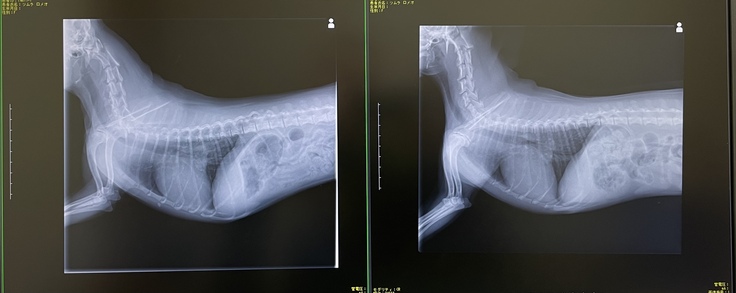

2021年7月心臓病の治療を専門とする病院でレントゲンと超音波検査をした結果、

「僧帽弁閉鎖不全症」「ステージB2」と診断されました。

左:2021年12月 右:2021年7月

左:2022年6月 右:2022年4月

しかし、2022年10月の定期健診で前回の検査時よりも心臓肥大がかなり進行しており、肺水腫になる可能性が非常に高いとの診断を受けました。

左:2022年10月 右:2022年6月